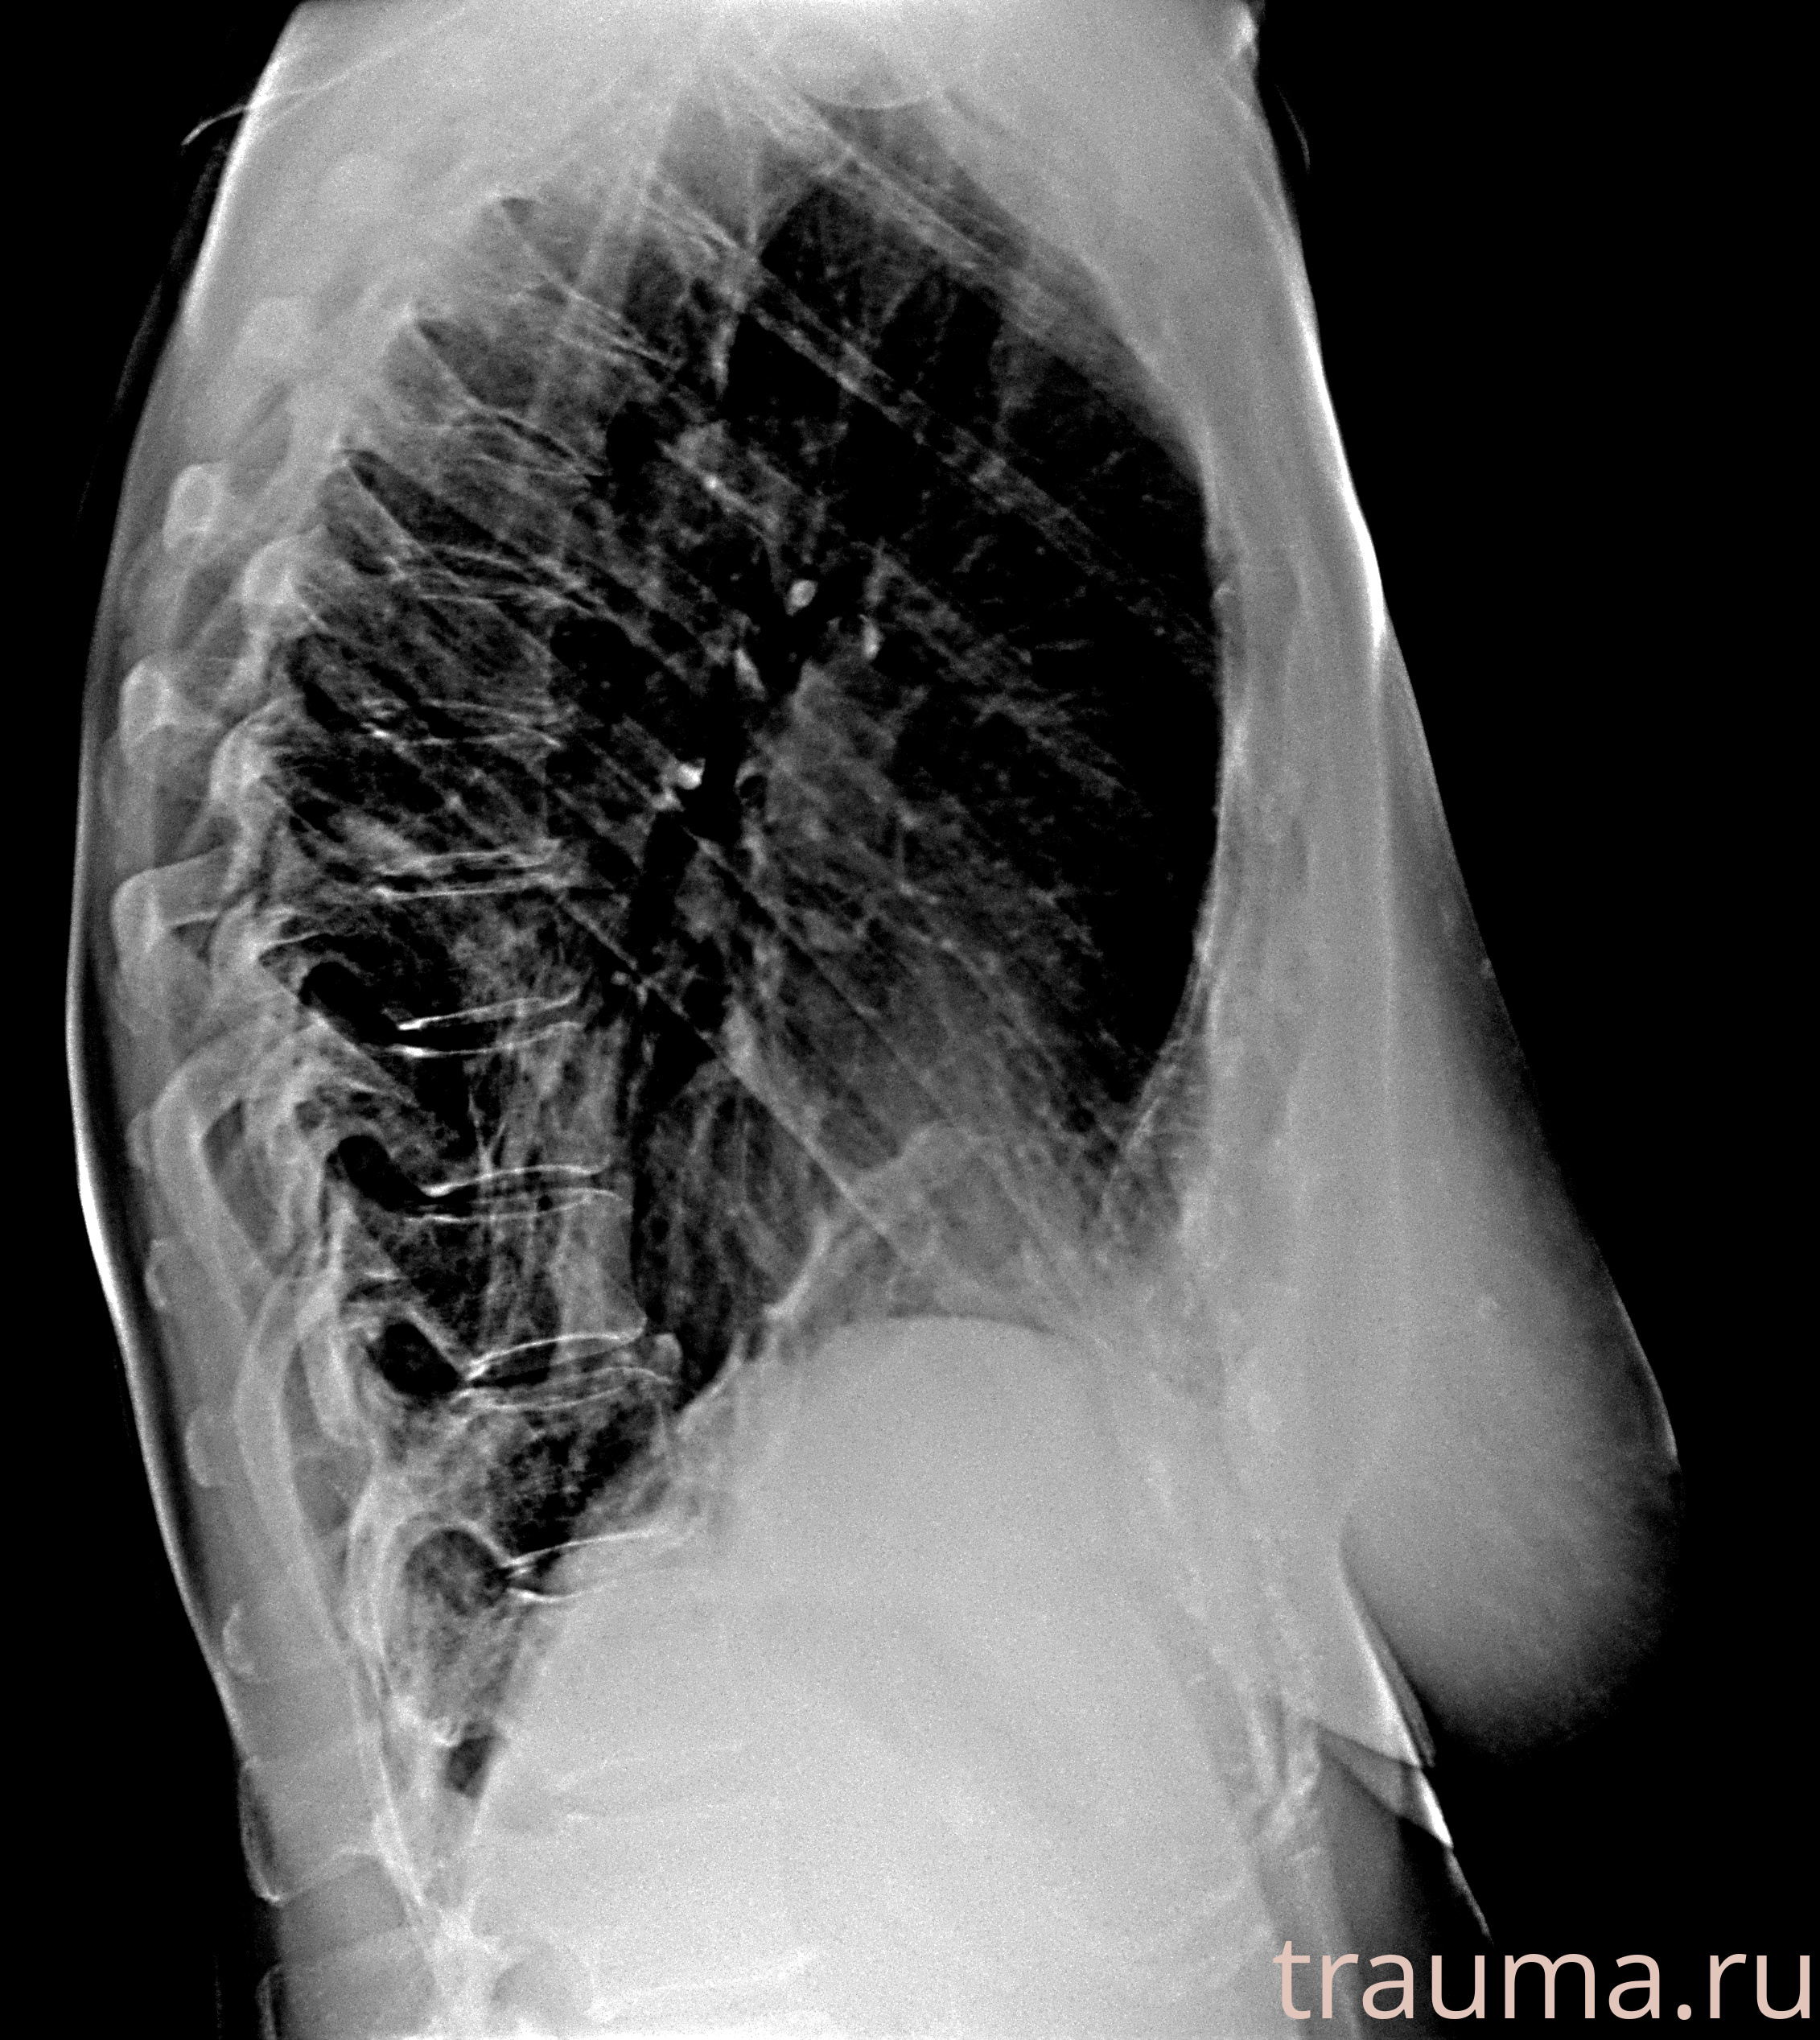

Рентгенограммы

Рентген на дому: по вашему адресу приезжает врач-рентгенолог, травматолог-ортопед с мобильным рентгеновским аппаратом, проводит диагностику травмы или заболевания, делает необходимые рентгенограммы, дает рекомендации по дальнейшему лечению. Получить качественные снимки в домашних условиях возможно благодаря уникальной методике, разработанной МосРентген Центром для института  Склифосовского

Яркость: 1   Контраст: 1   Инвертировать: 0 Увеличение: 1

Перетаскивайте мышь вверх/вниз для контраста, влево/право для яркости. Прокрутка колесом изменяет масштаб. Нажмите Сбросить для возврата к исходному изображению. При увеличении держите мышь в той области, которую хотите рассмотреть.